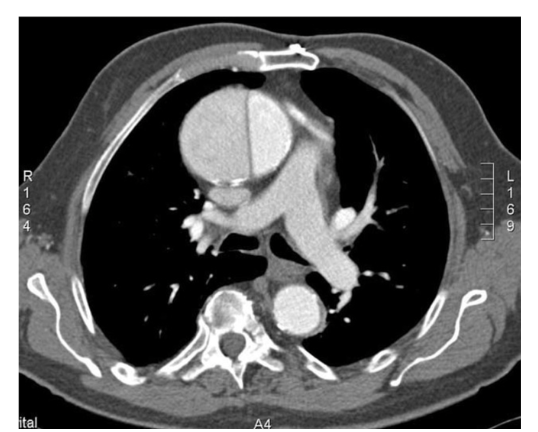

What is the protocol + pathology?

• CTPA

• There is max opacification within the pulmonary arteries therefore contrast was used and it’s in an EARLY arterial phase.

• Path = pulmonary embolism with an occlusion in the left pulmonary artery

• Filling defect characterised by hypodense streak within the left pulmonary artery.

• Coronal MIP = highest attenuation values within the voxel selected